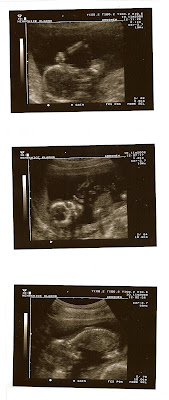

...a to druhé je pohled ultrazvukem na našeho mimíse...15+4...